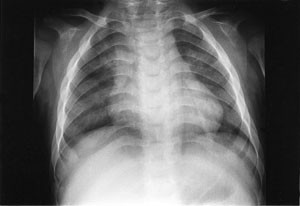

Pasienten ble så 13 måneder gammel innlagt i barneavdeling i forbindelse med ny feberepisode. Ved innleggelsen var han dystrofisk, med stor abdomen, tynne ekstremiteter og slunkne nates. Noe grove ansiktstrekk ble bemerket, men gav ikke umiddelbart videre assosiasjoner. Utredning av malabsorpsjon med tanke på cøliaki ble startet. Metabolsk screening av urin og serum ble rekvirert. Røntgen thorax viste klare lunger og et normalt stort hjerte, men påfallende brede costae (fig 1). Fysioterapeutisk vurdering bemerket en forsinket motorisk utvikling og stive ledd. Øre-nese-hals-undersøkelse viste betydelig nasalstenose og hypertrofiske tonsiller. Foreldrene kunne fortelle om uttalt pustebesvær og sterk snorking om natten, med tendens til pustestopp. Primær malabsorpsjon og cøliaki ble utelukket med serologiske prøver. Ultralyd abdomen viste leverstørrelse i øvre normalområde.